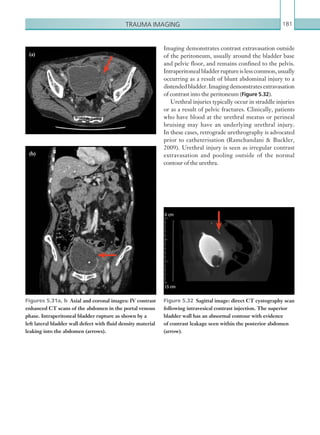

Gastrointestinal and genitourinaryimaging 33 Radiological findings Plain films The presence of free air under the diaphragm on an erect chest plain film is diagnostic of free intraperitoneal air (Figure 2.11). As little as 1 ml of air can be identified under the diaphragm. Care should be taken not to confuse the stomach bubble under the left hemidiaphragm with free air. Aplainabdominalfilmcanrevealabowelperforation, with the presence of Rigler’s sign (gas outlining both sides of the bowel wall) (Figure 2.12). Other abdominal plain film signs of free air include football sign (oval- shaped peritoneal gas), which is more common in children (Figure 2.13), increased lucency over the right upper quadrant (gas accumulating anterior to the liver) or the triangle sign (gas accumulating between three loops of bowel). Free gas can also be seen outlining ligaments in the abdomen, such as the falciform ligament (Figure 2.14). A left lateral decubitus film can also be used in the detection of small amounts of free air that may be interposed between the free edge of the liver and the lateral wall of the peritoneal cavity. Figure 2.11  AP semi-erect chest radiograph. Large volumes of gas can be seen underneath the diaphragm consistent with pneumoperitoneum. Figure 2.13  AP supine abdominal radiograph. A large, rounded lucency is seen projected in the ­mid-­abdomen representing free intra-abdominal gas in a ­non-dependent location. The falciform ligament is also seen outlined clearly by free gas (arrow). Figure 2.12  AP supine abdominal radiograph. Gas can be seen within the peritoneum on both sides of the bowel wall (Riggler’s sign), highlighting multiple loops of dilated small bowel. K22247_C002.indd 33 16/05/15 3:07 AM

• 56.

Chapter 234 Computed tomography Thefirst aim of the radiologist when interpreting an abdominal CT should be to identify the extraluminal air. Free air can be seen as small locules around the liver edge or within the peritoneum or as large collections of air that are difficult to identify as separate from bowel. Often, using a wide window (such as lung window settings) can help identify free air and distinguish between intra- and extraluminal gas. The next consideration is the location and distribution of air. The peritoneal cavity is divided into supra- and inframesocolic compartments by the transverse colon, and this distinction can be useful in radiological differentiation of upper and lower GI perforations. Subsequently, upper GI tract perforation (stomach or duodenal bulb) results in supramesocolic compartment gas and distal small and large bowel perforation in the inframesocolic compartments. Sections of the GI tract, such as stomach, first part of duodenum (5 cm), jejunum, ileum, caecum, appendix, transversecolon,sigmoidcolonandupperthirdrectum, are found within the peritoneal cavity; perforation of these sections results in intraperitoneal free air. The second and third parts of the duodenum, ascending and descending colon and middle third of rectum are retroperitoneal and fixed; they may therefore present with gas within the retroperitoneal compartment. Gastroduodenal perforation Peptic ulcer disease is a major cause of gastroduodenal perforation, followed by necrotic or ulcerated malignancies and iatrogenic and traumatic causes. Gastroduodenal perforation secondary to peptic ulcers is usually found in the gastric antrum and duodenal bulb. The descending and horizontal segments of the duodenum are common sites of perforation caused by blunt trauma because of their fixed attachment and/or compression against the vertebral column. Perforation sites can be demonstrated by the CT findings of ulceration or focal defect in the gastroduodenal wall (Figure 2.14), free air bubbles in contact with the stomach or duodenum, abrupt wall thickening associated with adjacent inflammatory fat stranding and localised free fluid between the duodenum and the pancreatic head. Figure 2.14  Axial image: IV contrast enhanced CT scan of the abdomen in the portal venous phase. Free intra-abdominal gas is seen anteriorly. A large defect is seen along the anterior wall of the stomach as a result of peptic ulcer disease, causing perforation (arrow). Small bowel perforation Small bowel perforation is rare; small amounts of free air along the anterior peritoneal surfaces of the liver and mid-abdomen and among the peritoneal folds are usually indicative. Non-specific CT findings, such as mural thickening and abnormal enhancement of the small bowel, mesenteric fluid and mesenteric stranding, should be considered suspicious in patients with suspected small bowel perforation. Large bowel perforation Perforation sites in colonic loops can frequently be correlated with their causes. Malignant neoplasm, diverticulitis (Figure 2.15), blunt trauma and ischaemia are common causes of perforation on the left-sided colon. Inflammatory bowel disease and penetrating trauma tend to be seen in the right-sided colon. The caecum is especially prone to perforate in patients with mechanical colonic obstruction. K22247_C002.indd 34 16/05/15 3:07 AM

• 57.

Gastrointestinal and genitourinaryimaging 35 oesophageal/trachealbronchialinjury,intra-abdominal drainsandhysteroscopycanexplainfreeintraperitoneal or retroperitoneal air in the absence of a GI tract perforation. The amount of air in the postoperative period is variable, but should be less than 10 ml in the majority of cases and negligible after day 10. Large volumes of free air in the postoperative period should be considered suspicious for anastomotic leaks. When detected, bowel perforation on any imaging modality should be immediately communicated to the surgical team for consideration of surgery, and a record of this should be made at the end of the report. Key points • Plain films (erect CXR and AXR) are useful for suspected bowel perforation and they can detect free intra-abdominal air. • The main aim of CT imaging is to identify free air and associated inflammatory stranding in order to locate the site of perforation. The distribution of air can help to achieve this. • Be aware that free air within the peritoneal cavity may be from sources other than bowel (e.g. iatrogenic). A review of the clinical history is imperative. • Bowel perforation is an urgent finding that may necessitate surgical intervention. Findings should be communicated promptly and directly to the clinical team. Report checklist • In the presence of free gas, identify the potential perforated site. • Presence or absence of underlying causes such as diverticulitis, bowel malignancy and bowel ischaemia. When perforation occurs owing to diverticulitis or colorectal malignancy without bowel obstruction, the quantityoffreeairisusuallysmallandloculesofairtend to be concentrated in close proximity to the involved colonic loops. The presence of free air, phlegmon and/or an abscess, an extraluminal collection and the underlying colonic abnormality (neoplasm) should be carefully evaluated on CT scans. A review of the clinical history is important when reviewing CT for suspected bowel perforation. A history of recent surgery (laparoscopic or open), Figure 2.15  Axial image: IV contrast enhanced CT scan of the pelvis in the portal venous phase. Locules of extraluminal gas are seen adjacent to the sigmoid colon at the site of diverticular perforation, in addition to a contained abscess at this site. K22247_C002.indd 35 16/05/15 3:07 AM

• 58.

Chapter 236 Inflammatory boweldisease is subdivided into Crohn’s disease, ulcerative colitis and indeterminate inflammatory colitis (which demonstrates features of both Crohn’s disease and ulcerative colitis). Crohn’s disease and ulcerative colitis classically differ in the distribution and extent of inflammation. Ulcerative colitis causes inflammation limited to the mucosa, initially involves the rectum and can extend proximally to involve the entire colon. Inflammation is continuous and small bowel involvement is not typical, although involvement of the ileum can be seen with associated backwash ileitis. In contradistinction, Crohn’s disease causes transmural inflammation, can involve any aspect of the GI tract and commonly demonstrates skip lesions. Whilst a more common cause of colitis in younger demographics than ischaemic colitis, inflammatory bowel disease has a bimodal distribution ofonsetand,assuch,increasingageshouldnotdissuade from the diagnosis. Infectivecolitiscanarisesecondarytomanydifferent causative organisms and can occur in any demographic. Of particular importance in the hospital environment is pseudomembranous colitis, which is caused by an overgrowth of Clostridium difficile, which usually develops secondary to antibiotic administration. Neutropaenic colitis (typhilitis) can be another iatrogenic form of colitis, occurring in immunosuppressed patients, commonly secondary to chemotherapy. Radiological investigations CT is the imaging modality of choice in the investigation of bowel ischaemia, although there are conflicting reports of its sensitivity and specificity. The addition of an arterial phase to the standard portal venous phase of the abdomen and pelvis has been shown to increase specificity. Oral contrast should not be administered since it can make appreciation of bowel wall enhancement more difficult. It is important to note that a ‘normal’ CT study cannot definitively exclude bowel ischaemia, and it can often be difficult to reliably differentiate bowel ischaemia from other forms of colitis. Abdominal plain film imaging is often performed initially and can be helpful; however, this has a low sensitivity and specificity, cannot differentiate between the causes of colitis and rarely negates the BOWEL ISCHAEMIA AND ENTEROCOLITIS Acute, occlusive bowel ischaemia carries a high morbidity and mortality rate and is a surgical emergency. This condition must be separated from chronic, non-occlusive ischaemia, which carries a much lower mortality rate and occurs secondary to incomplete vessel occlusion. Ischaemia can be both arterial and venous in nature. Arterial causes include atherosclerosis, emboli, vasculitis and low-flow states (i.e. the causes of hypotension). Typically, the location of arterial ischaemia is dictated by the vascular anatomy of the bowel. The SMA supplies the small bowel, the ascending colon and the proximal transverse colon. The IMA supplies the distal transverse colon, the descendingcolonandthesigmoidandproximalrectum (splenic flexure to rectum). The splenic flexure and rectosigmoid junction are termed ‘watershed areas’ and are particularly susceptible to ischaemia caused by low- flow states. Bowel ischaemia typically affects the middle aged to elderlypopulationbecauseofincreasingatherosclerotic burden.Acutebowelischaemiaclassicallypresentswith abdominal pain that is disproportionate to the clinical findings, although this is not a reliable enough sign to differentiateitfromotherintra-abdominalpathologies. Lactate elevation is a sensitive but non-specific marker for ongoing acute bowel ischaemia and can also be helpful.Ahistoryofabdominalangina,atrialfibrillation and atherosclerotic disease should always prompt suspicionofacutebowelischaemiaandurgentdiagnosis is vital to facilitate surgical resection/revascularisation. Depending on the degree of clinical suspicion, patients may proceed to diagnostic laparotomy without radiological input, although increasingly imaging is being utilised prior to definitive treatment. The diagnosis of acute bowel ischaemia is a challenging one for the on-call radiologist. There is a significant overlap in the findings seen in both acute bowel ischaemia and other inflammatory and infective aetiologies of enterocolitis. While urgent imaging is oftennotrequiredintheemergencysettingtodiagnose inflammatory and infective causes (the diagnosis of these is made with endoscopy and microbiological analysis, respectively), they are discussed subsequently due to the imaging overlap. K22247_C002.indd 36 16/05/15 3:07 AM

• 59.